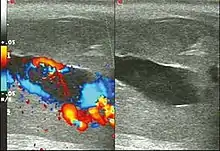

Priapism is defined as a painful and prolonged penile erection, with or without sexual stimulation. Color Doppler ultrasound is the imaging method of choice for the investigation of priapism, because it is noninvasive, widely available, and highly sensitive. By means of this method, it is possible to diagnose priapism and differentiate between its low- and high-flow forms.[1]